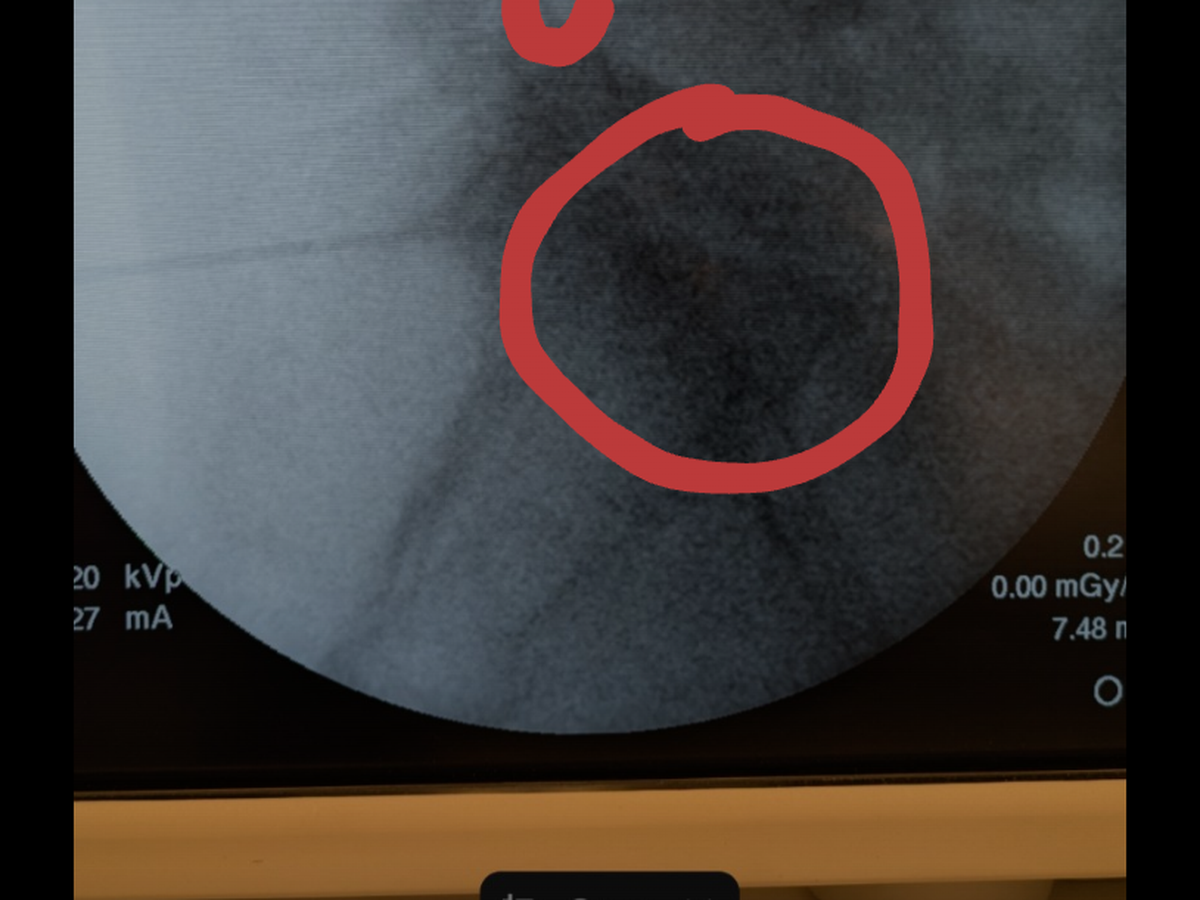

Hello, my name is Carmina Mora. I have been dealing with ongoing back and other medical issues, which have not only caused me significant discomfort and pain but have also resulted in financial hardship due to the amount of time I had to take off work.

I was advised over a year ago that I needed back surgery, but due to financial constraints, I was unable to proceed with it at the time. Unfortunately, my condition has since worsened to the point where surgery is now essential, and I had scheduled the procedure for April 4.